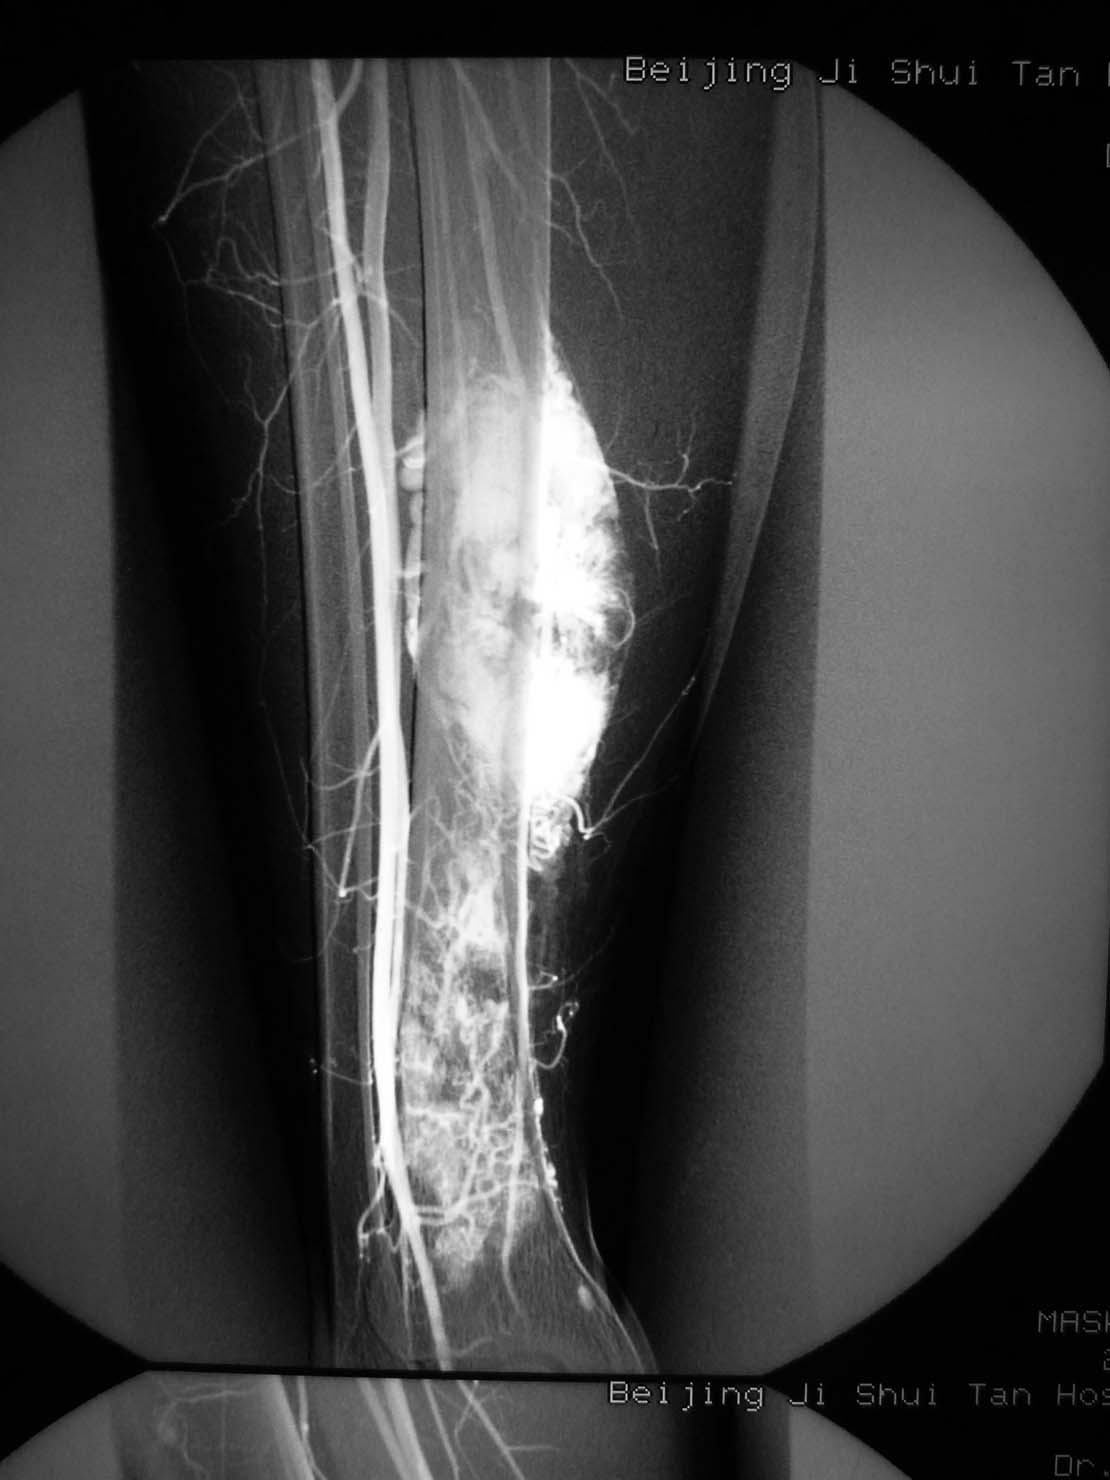

病理结果,腺泡样软组织肉瘤!

腺泡样软组织肉瘤

极为罕见,其组织来源不明。

起源于肢体软组织者称腺泡状软组织肉瘤,原发于骨内者,称骨腺泡状肉瘤。

本病大多发生于股部、臀部及小腿深侧肌群,上肢和其他部位少见。

x线平片:圆形或卵圆形软组织肿块影,基底部与病骨相连。

肿瘤内可见斑点状或细小结节状钙化。

骨质破坏大多表现为溶骨性地图状或虫噬性破坏,并常伴有层状骨膜反应。

mr检查:t1和t2加权像均显示肿瘤组织呈分叶状高信号强度,并见肿瘤内有低信号间隔。